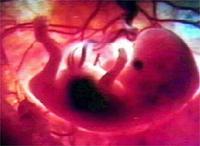

5周人胚胎2、第二個月末,四肢已形成,手指足趾明顯。

4、胚長約30mm,重3~4g,但可器官系統原基已奠定。